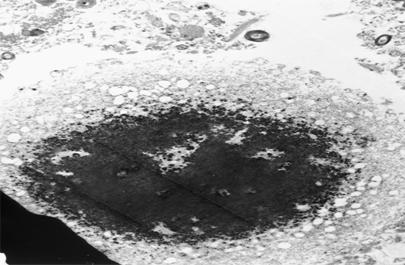

Après 5 à 10 ans de traitement peuvent survenir des complications contre lesquelles les traitements médicamenteux ont du mal à lutter : il s’agit des phases on-off (alternance de phase de mobilité et de phase d’akinésie en lien avec les fluctuations de quantité de médicament au cours de la journée) et des mouvements anormaux (dyskinésies »).

C’est à ce stade que la stimulation cérébrale profonde a fait la preuve de son intérêt : il s’agit d’implanter des électrodes dans le noyau subthalamique, dans la base du cerveau, afin d’émettre des impulsions électriques grâce à un boitier implanté sous la peau.Ces électrodes sont implantées en neurochirurgie stéréotaxique ce qui fait que cette technique est réservée aux malades les plus handicapés et capable de supporter la chirurgie (moins de 70 ans le plus souvent).